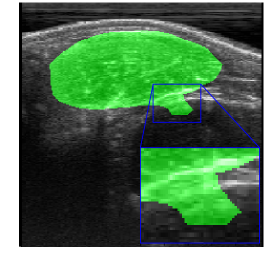

Rib Eye Area (REA). This image dataset consists of ultrasound images of the Longissimus dorsi muscle between the 11th and 13th ribs of cattle. The goal is to automatically calculate the rib eye area (REA), an important region for decision making during cattle breeding. The main challenge is the uncertainty in the REA annotation, since the image is noisy and even experts have difficulty in delimiting the borders of this region. Fig. 3 presents examples of images and the annotation made by a specialist. We can observe that some borders are absent and depend on the subjectivity and knowledge of the annotator. To evaluate the segmentation methods, 76 images with resolution were obtained and labeled by an expert. Due to the number of images, the division of the images in training and testing followed 5-fold cross-validation.

REA dataset. This image dataset has high uncertainty during labeling due to noise from the ultrasound image. In some cases, the border of REA is not completely visible and must be estimated by the specialist. Therefore, the proposed approach becomes essential to obtain accurate segmentation at the edges. The segmentation examples in Fig. 6 show that the baseline was not able to define the REA correctly due to the uncertainty of the labeling. On the other hand, the proposed approach presents results close to the specialist in regions that the border needs to be estimated.